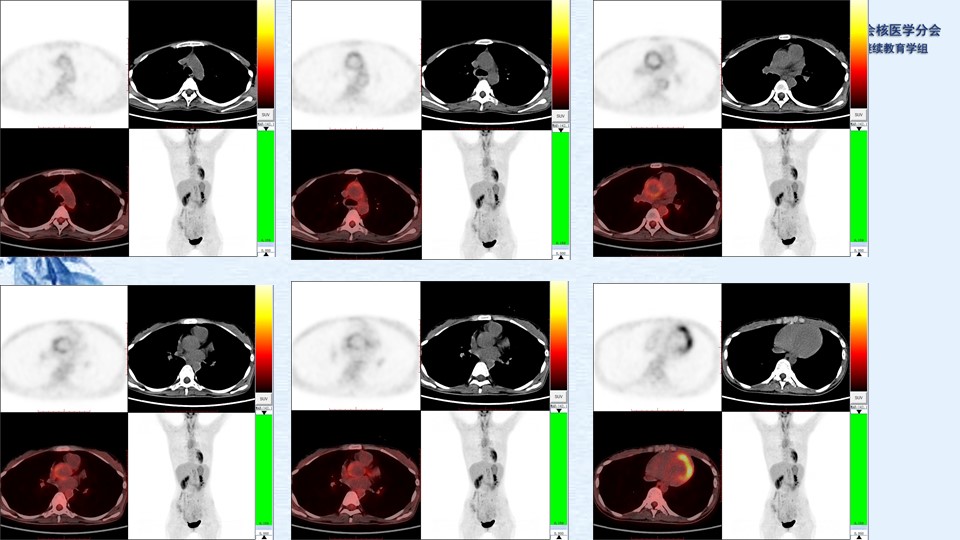

病例94:大动脉炎累及冠脉PET显像一例-李薇